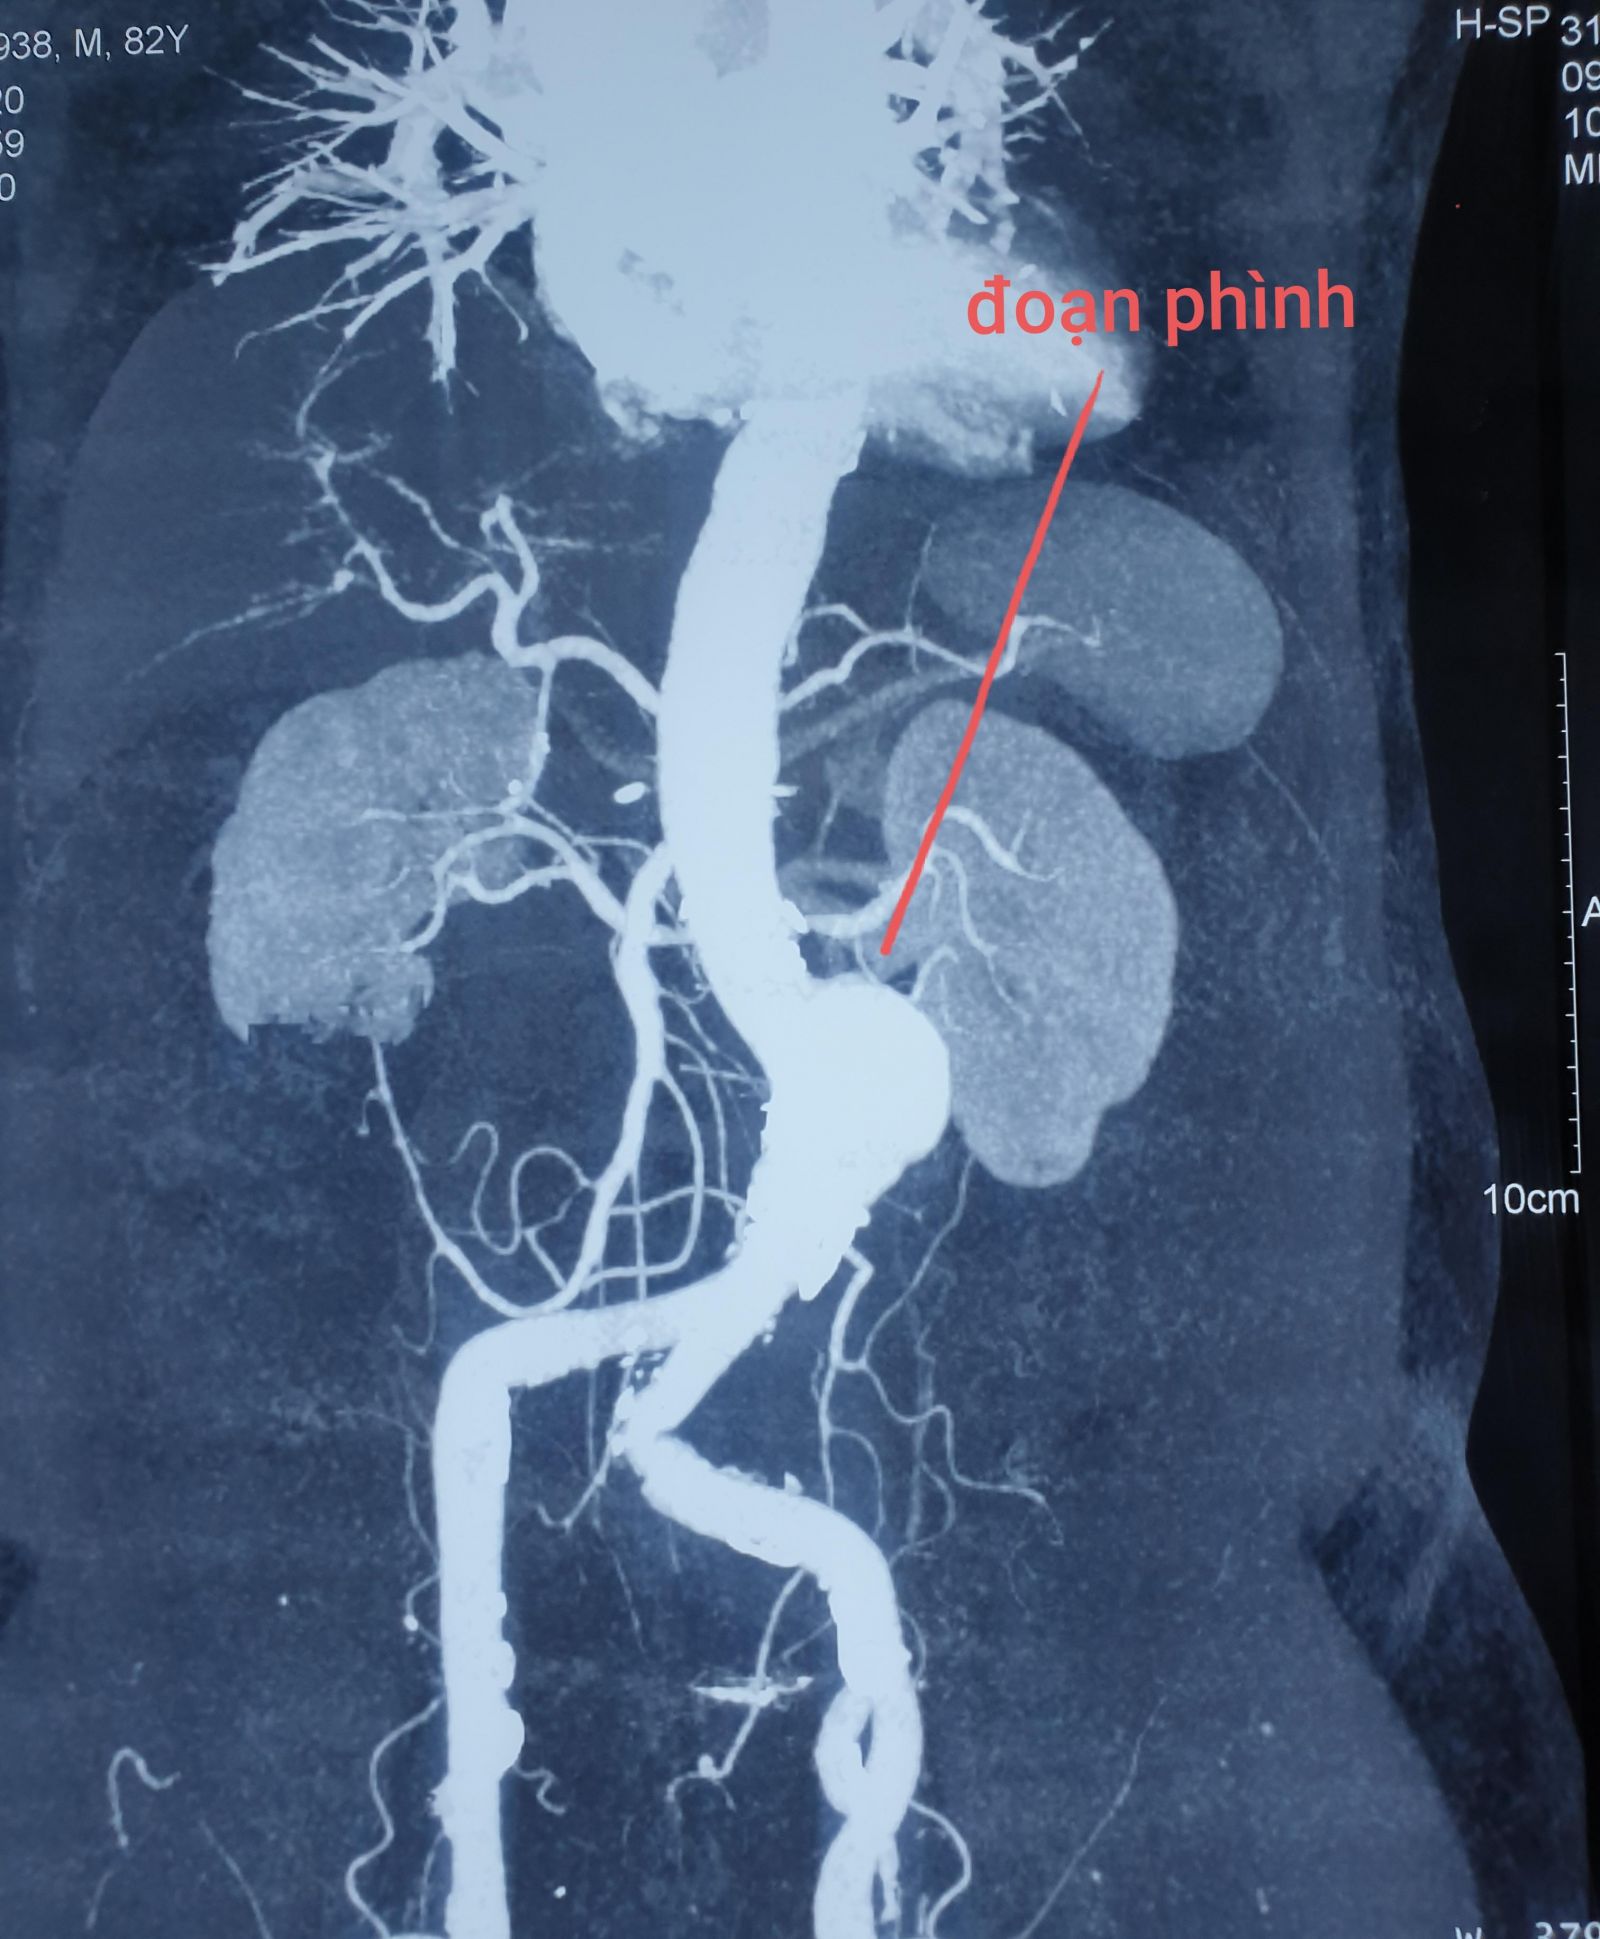

Hình chụp MSCT cho thấy đoạn phình cách động mạch thận 13mm, đường kính 50mm dài 120mm. Các bác sĩ chuyên khoa tim mạch tiến hành can thiệp, đặt stent graft cho bệnh nhân. Sau can thiệp, sức khỏe ông cụ phục hồi tốt, vừa được xuất viện.